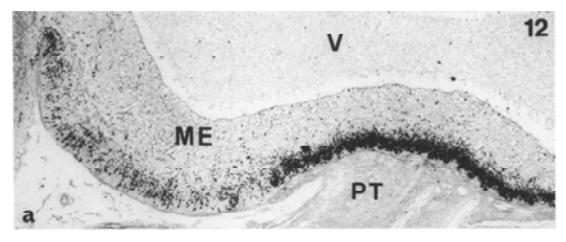

Gonadotropin Releasing Hormone (GnRH), also know as Luteinizing-hormone-releasing-hormone (LHRH) and luliberin, is a tropic peptide hormone responsible for the release of follicle-stimulating hormone (FSH) and Luteinizing Hormone (LH) from the anterior pituitary. GnRH is synthesized and released from neurons within the hypothalamus. The peptide belongs to gonadotropin-releasing hormone family.